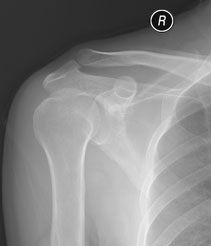

[face=黑体]请大家看看位置不一样的结果[/face]

请大家看看位置不一样的结果